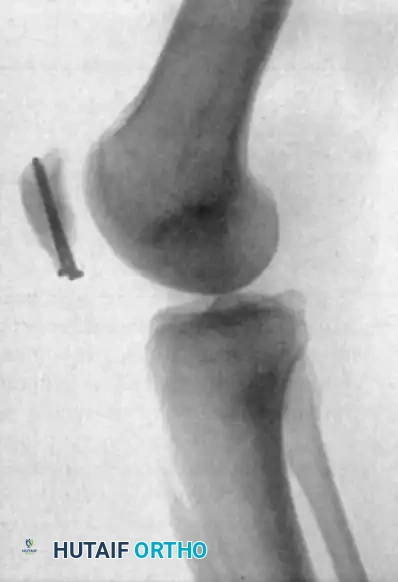

Clinical Pearl: Radiographic evaluation of the patellofemoral joint can offer clues to impending rupture. Degenerative spurring at the superior or inferior poles of the patella—often referred to as the "tooth sign" on a tangential (skyline) view—indicates chronic traction tendinopathy and significant structural changes within the quadriceps or patellar mechanism.

FIGURE 48-29: Degenerative spurring (the "tooth sign") visualized on a tangential view of the patella. This radiographic finding is highly indicative of significant, chronic degenerative changes within the quadriceps mechanism.